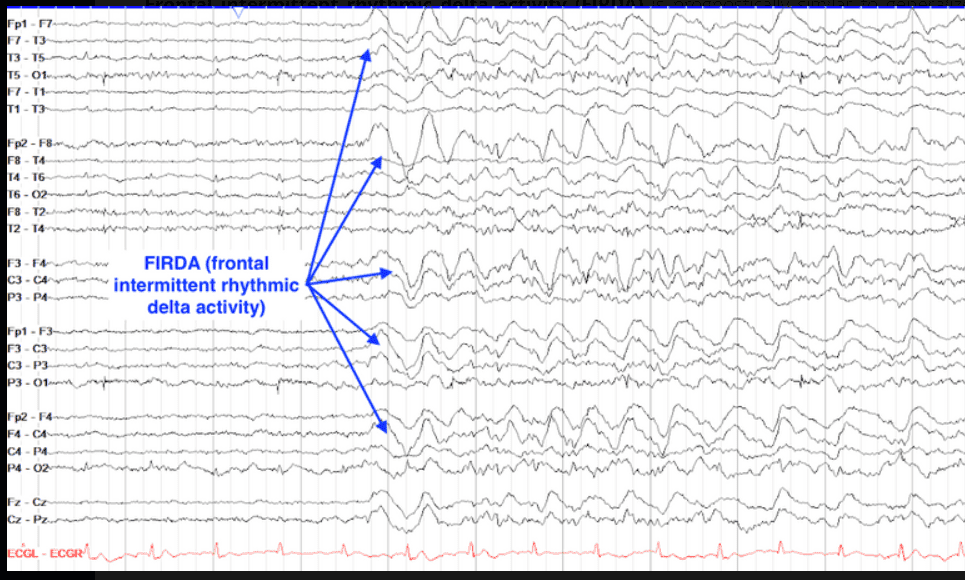

EEG waveform and diagnosis

Frontally dominant generalized rhythmic delta activity - frontal intermittent rhythmic delta activity - 2-3 Hz high amplitude rhythmic to semirhythmic activity with anterior predominance

Midline cerebral pathology: 3 ventricle region tumor

Nonspecific in encephalopathic EEG

Frontal intermittent rhythmic delta activity (FRIDA): frontal cerebellar dysfunction

1-4 Hz, up to 2 seconds, always bilateral

Metabolic encephalopathy, neurodegenerative disease, hypoxic encephalopathy, infections and encephalitis